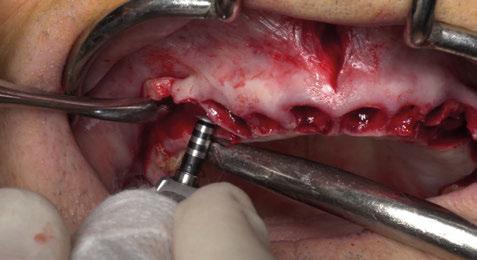

Figura 18. Procedimiento quirúrgico. a) customización de la lámina de cortical acorde a las características del defecto (Lámina de cortical desmineralizada Cortiflex® Salugraft Dental). b) fijación de la lámina cortical con microtornillos.

En este sentido, vuelve a realizarse el mismo protocolo de materiales que en el primer caso clínico. Es decir, en primer lugar se sutura un injerto de tejido conectivo al colgajo; posteriormente se utiliza un injerto óseo alogénico particulado (OraGRAFT® Aloinjerto Cortical Particulado MIX 70% Mineralizado / 30% Desmineralizado) para reconstruir la dehiscencia ósea además de preservar el escaso alveolo del diente extraído; y adicionalmente se utiliza la lámina de cortical desmineralizada (Lámina de cortical desmineralizada Cortiflex® Salugraft Dental).

La sutura realizada en este procedimiento quirúrgico es idéntica a la del primer caso clínico.